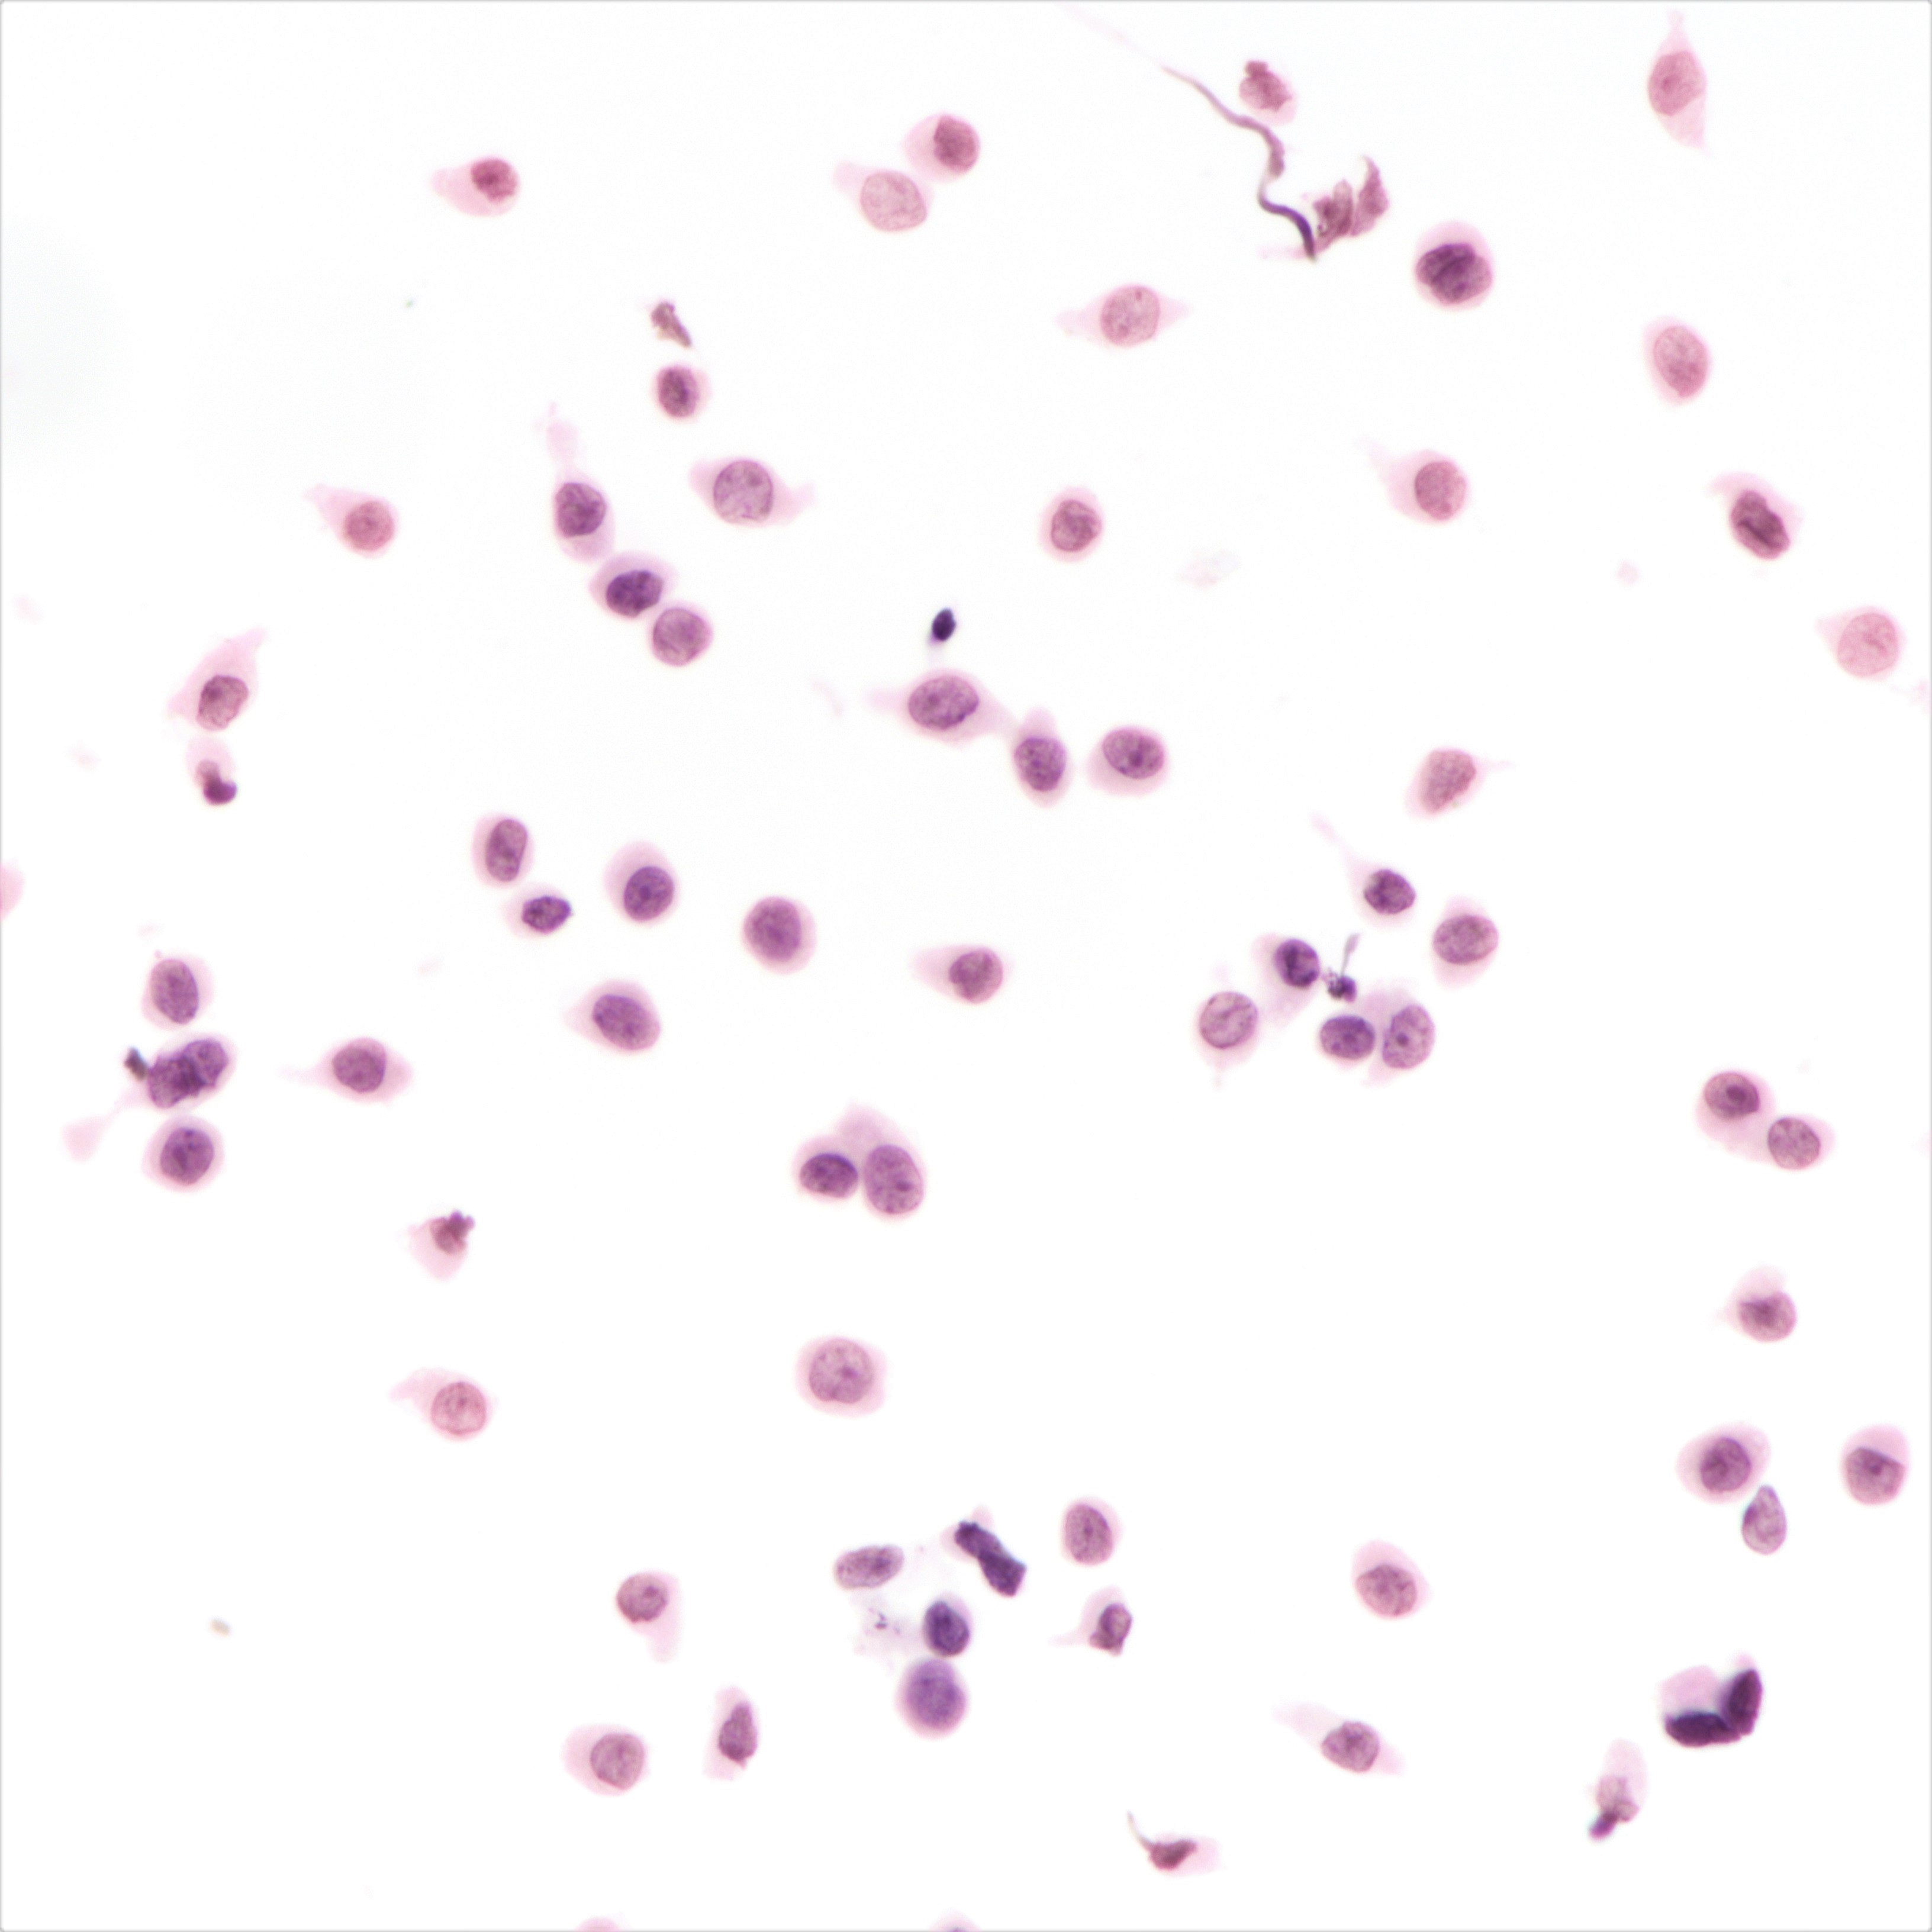

Cytology description

- Cellularity can be low

- Tumor cells arranged in chains, single files or as single cells

- Tumor cells arranged in small chains are helpful clues

- Nuclear atypia mostly mild

- Nuclei round to oval and eccentric

- Cytoplasm scanty with a high nuclear / cytoplasmic ratio

- Occasional intracytoplasmic vacuolations may be seen

- Cytologic features can resemble mesothelial cells in effusion fluid (Diagn Cytopathol 2012;40:311)

Cytology images